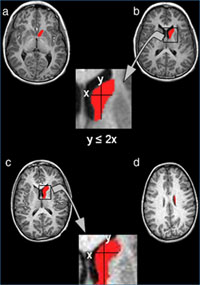

En vermell està pintat el nucli caudat, a la part superior el cap i a la part inferior el cos. La fórmula indica el mètode per separar el cap del cos.

El primer estudi citat pel “Consensus report” va ser publicat l’any 2008 a la revista Psychiatry Research: Neuroimaging. El grup va fixar la seva investigació en el nucli caudat, una de les principals estructures cerebrals involucrades en l’aprenentage i la memòria, que té tres parts: el cap, el cos i la cua. S’havia comprovat que el nucli caudat estava alterat en els pacients amb TDAH, tot i que la literatura prèvia presentava resultats contradictoris sobre quines eren les alteracions concretes. El grup del Dr Vilarroya va descobrir que els pacients amb TDAH presentaven una alteració entre el cap i el cos del nucli caudat que no es veia en els subjectes controls. Amb el desenvolupament d’un nou mètode de segmentació del nucli caudat, entre el cap i el cos es va poder mostrar que els pacients amb TDAH presentaven un nucli caudat dret més petit, fonamentalment degut a una disminució en el cos, que no el cap, del nucli caudat.